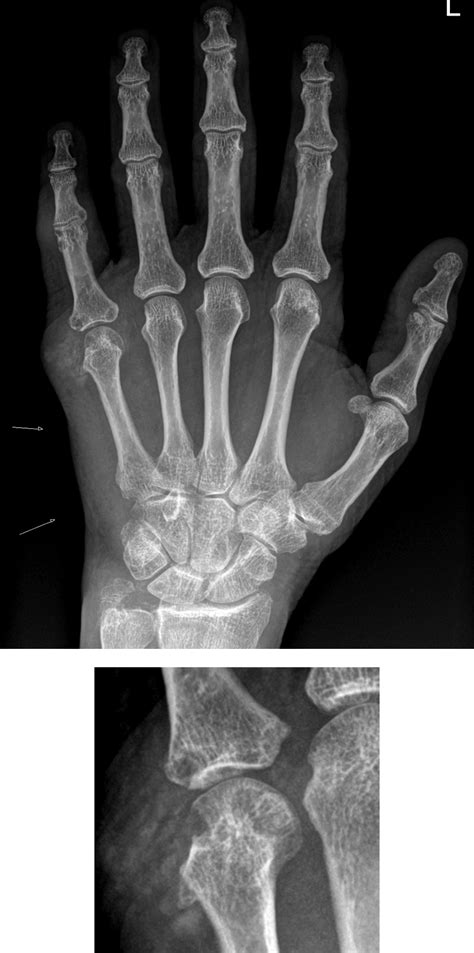

• Rheumatoid Arthritis: A chronic inflammatory autoimmune disorder where the immune system attacks the joint lining.

• Medical Imaging: X-rays are standard for assessing bone integrity, while MRI scans are superior for identifying soft tissue or cartilage damage.